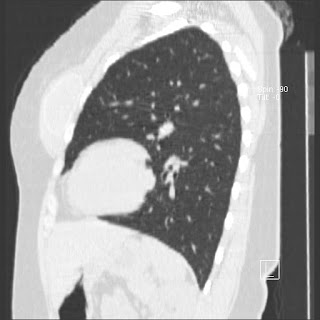

New CT images (without contrast) for 40 year old female with silicone breast implants. Formal diagnosis is expected soon. Images from 2010 can be seen here http://radiology-images.blogspot.com/p/40-year-old-female-silicone-implants.html